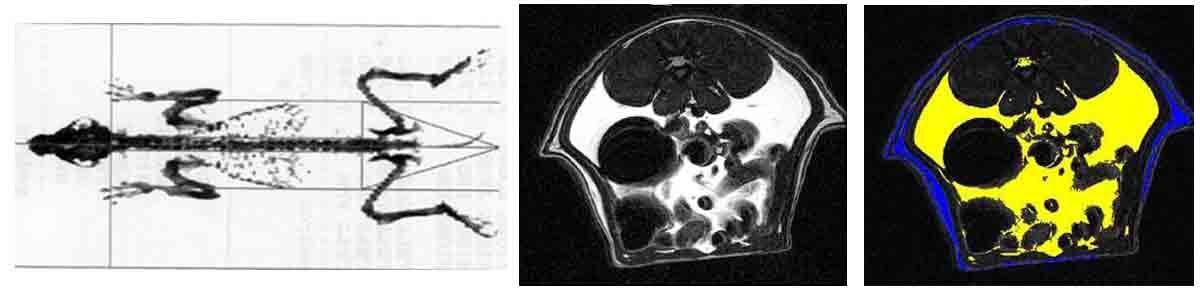

Whole body imaging protocols are used for assessing the effects of therapeutics on metabolism and feeding behavior. Using dual energy x-ray absorptiometry (DEXA) body composition can be determined non invasively in longitudinal studies. These studies give body composition in terms of the percentage of fat, lean and bone tissue. Body composition is an important component in obesity studies.

From left to right: DEXA image of a dog; MR Image of rat abdomen; MR image segmented into visceral (yellow) and subcutaneous (blue) fat.